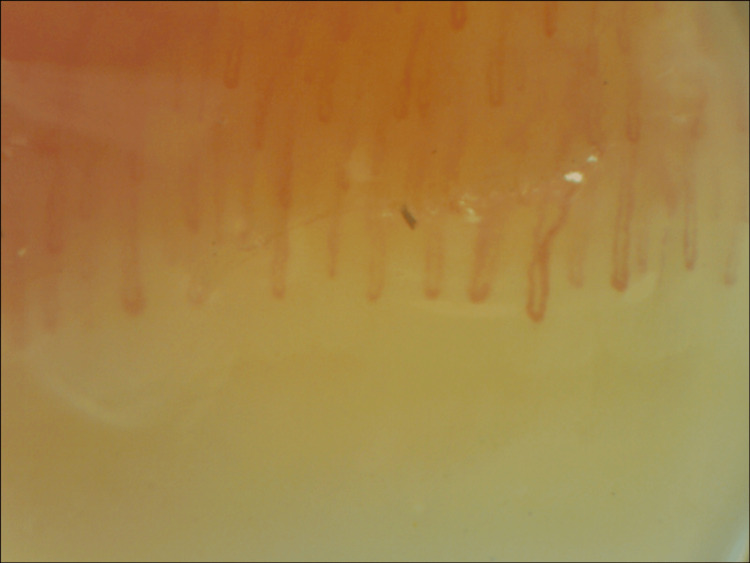

To investigate a possible underlying cause for this Raynaud’s phenomenon, further tests were requested. Complete blood cell count and biochemistry with muscle enzymes were normal. There were no vitamin or iron deficiencies. Thyroid hormones were within normal range. Laboratory tests were negative for antinuclear antibodies, as well as anti-double-stranded DNA (anti-dsDNA), anti-centromere, anti-SCL-70, anti-RNA polymerase III, anti-ribonucleoprotein (anti-RNP), anti-La/Sjogren’s syndrome B (SSB), and anti-Sjogren’s syndrome A (SSA)/Ro antibodies. Immunoglobulins and complement levels were within normal limits. Serological tests were negative for hepatitis virus B and C, human immunodeficiency virus (HIV), herpes simplex virus (HSV), Epstein-Barr virus (EBV), Chlamydia trachomatis, Borrelia, Rickettsia, and Coxiella. Interferon-gamma release assay (IGRA) was also negative. Chest X-ray showed no abnormalities, lung function tests were normal, and chest, abdominal, and pelvic computed tomography showed no malignancy or other pathological findings that could justify a paraneoplastic RP. Magnetic resonance excluded sacroiliitis, and no inflammatory activity was identified in the PET scan. Subclavian Doppler ultrasound showed normal filling of the lumen, and the Doppler study was normal. Nailfold capillaroscopy (Figure 2) revealed non-specific changes bilaterally, such as capillary enlargement (34-49 microns), without megacapillaries, rare capillary tortuosity, a few small traumatic hemorrhages, and pericapillary edema, with normal density (10 capillaries/mm2) and no avascular areas. These changes were compatible with a non-scleroderma-like pattern.

Figure 2. Nailfold capillaroscopy before treatment.

One-year follow-up capillaroscopy (Figure 4) showed significant improvement in capillary enlargement and less tortuosity, with most capillaries being normal in shape and size.

Figure 4. Nailfold capillaroscopy after treatment.